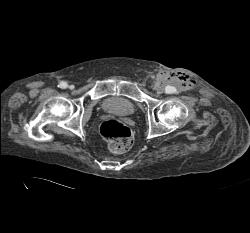

Hardware Extends and Adjacent to Aorta